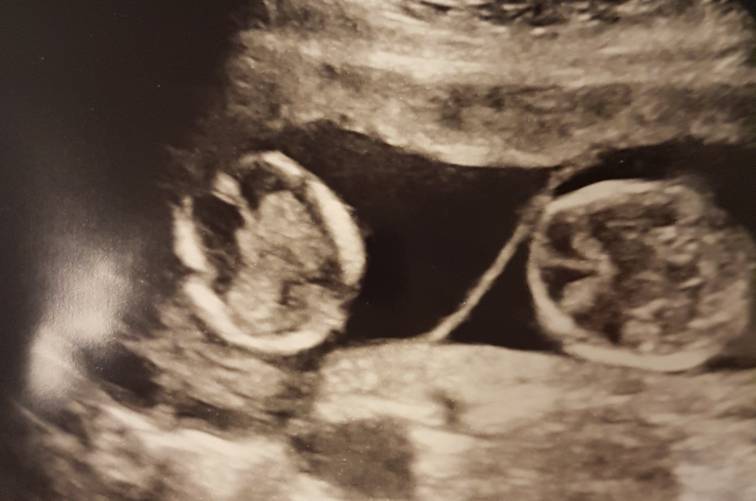

Moi chlopcy zaszczepieni. Dzis 3,5msc od porodu maja M 6kg, 59cm; B 5850g 61cm. Poszlam ich zaszczepić sama i zaluje, bo sie darli a dwoch jednocześnie nie dalam rady uspokajac. Ledwo zyje. Dobrze ze po powrocie zasneli i juz 2h spia, a ja moge odsapnac.